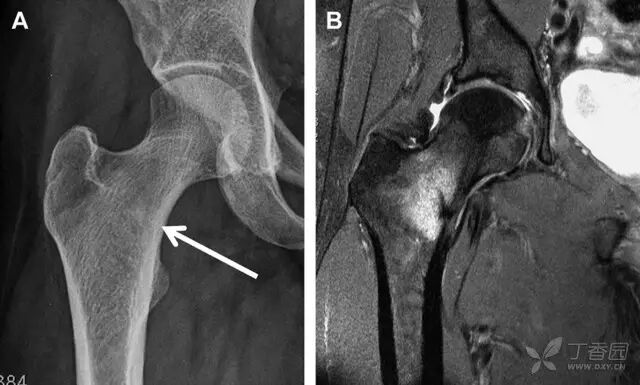

本文是根据吴新宝教授髋臼骨折手术治疗技术课程内容整理而成,有删节,为课程内容的一小部分。